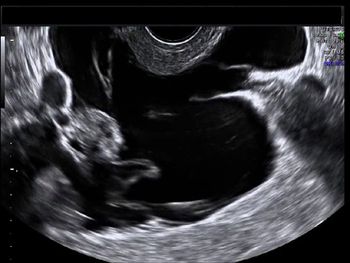

Challenge your diagnostic skills: What abnormality do you see in this woman with a history of ectopic pregnancy?